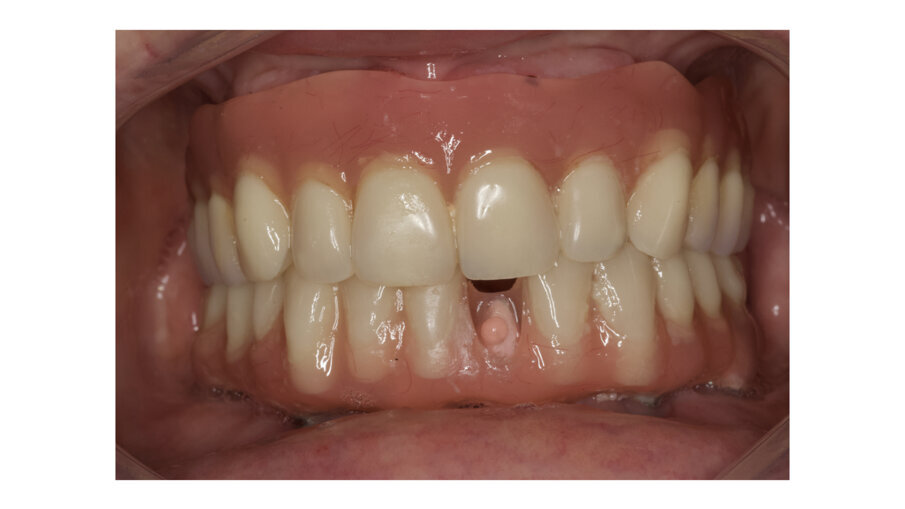

During daily practice, it is very common to face situations where the implant has to be placed lingually due to normal resorption (Fig. 1) of the buccal plate after the extraction. But, at the same time, it is not necessary to perform bone grafting procedures. The result of this scenario is to increase the stress on the implant-bone complex when we use rigid materials like conventional ceramics (Fig. 2). For this daily practice situation, the combination of rigid and resilient materials against the antagonist, allows the stress to the implant-bone complex to be reduced (Figs. 3, 4).

Fig. 4: Implant crown after one week of placement.

Fig. 5: Implant crown after placement.